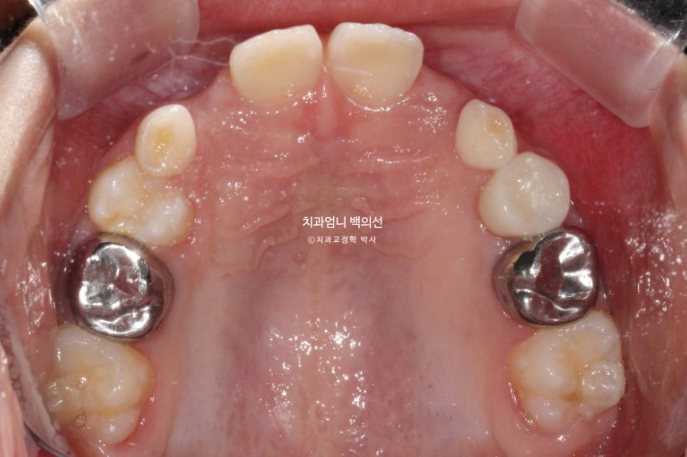

23년 12월 교정치료를 위해 내원한 만 8세 어린이 입니다.

타치과에서 반대교합, 비대칭, 공간이 부족하여 앞니가 못 나오고 있다는 이야기를 듣고 교정을 위해 내원했습니다.

중심선이 많이 어긋나 있으며 파란화살표는 위아래가 거꾸로 물리는 반대교합입니다.

노란색 아래턱의 중심, 흰색이 윗턱의 중심선입니다.

아래턱이 치아중심선 만큼 왼쪽으로 틀어진 비대칭입니다.

유치송곳니끼리 거꾸로 물리는 상태라 이 부분에 교합간섭이 있습니다.

윗니가 아랫니를 덮지 못하는 절단교합입니다.

측절치와 송곳니날 자리가 부족해서 악궁확장도 필요한 상황입니다.